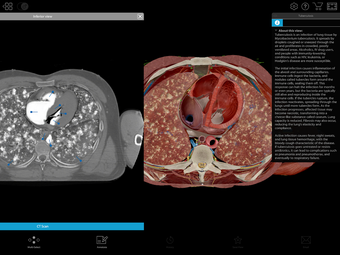

Physiology & Pathology is a comprehensive application that provides an interactive guide to human anatomy. Developed by Visible Body, this Android application is a full version licensed program that falls under the lifestyle category of medical subcategories. With more than 5,800 3D models, 38 animations, 16 illustrations, and 26 quizzes, this application covers 48 physiology topics and 57 conditions, allowing users to explore the step-by-step breakdown of common cardiovascular, renal, respiratory, gastrointestinal, and musculoskeletal processes.

One of the most remarkable features of this application is that it enables users to compare 3D models of normal anatomy with models of common diseases and conditions. Furthermore, users can set the heart rate and visualize conduction in a dissectable, beating 3D heart while following along on an ECG. The application also presents animations that demonstrate the physiological processes of gas exchange, pulmonary ventilation, fluid balance, peristalsis, and more. Interactive lessons walk users through the progression of atherosclerosis, kidney stones, lung cancer, and other common conditions, and quizzes test users' knowledge of various physiological processes and pathologies.